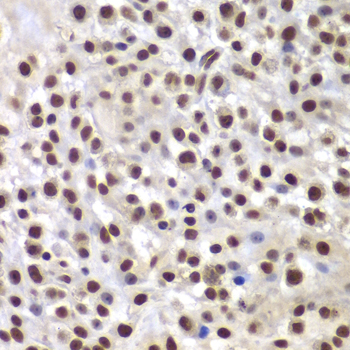

DescriptionSMARCB1 Polyclonal Antibody. Unconjugated. Raised in: Rabbit.

ImmunogenA synthetic peptide corresponding to a sequence within amino acids 50-150 of human SMARCB1/SNF5 (NP_003064.2)

ApplicationWB, IHC, IF, IP